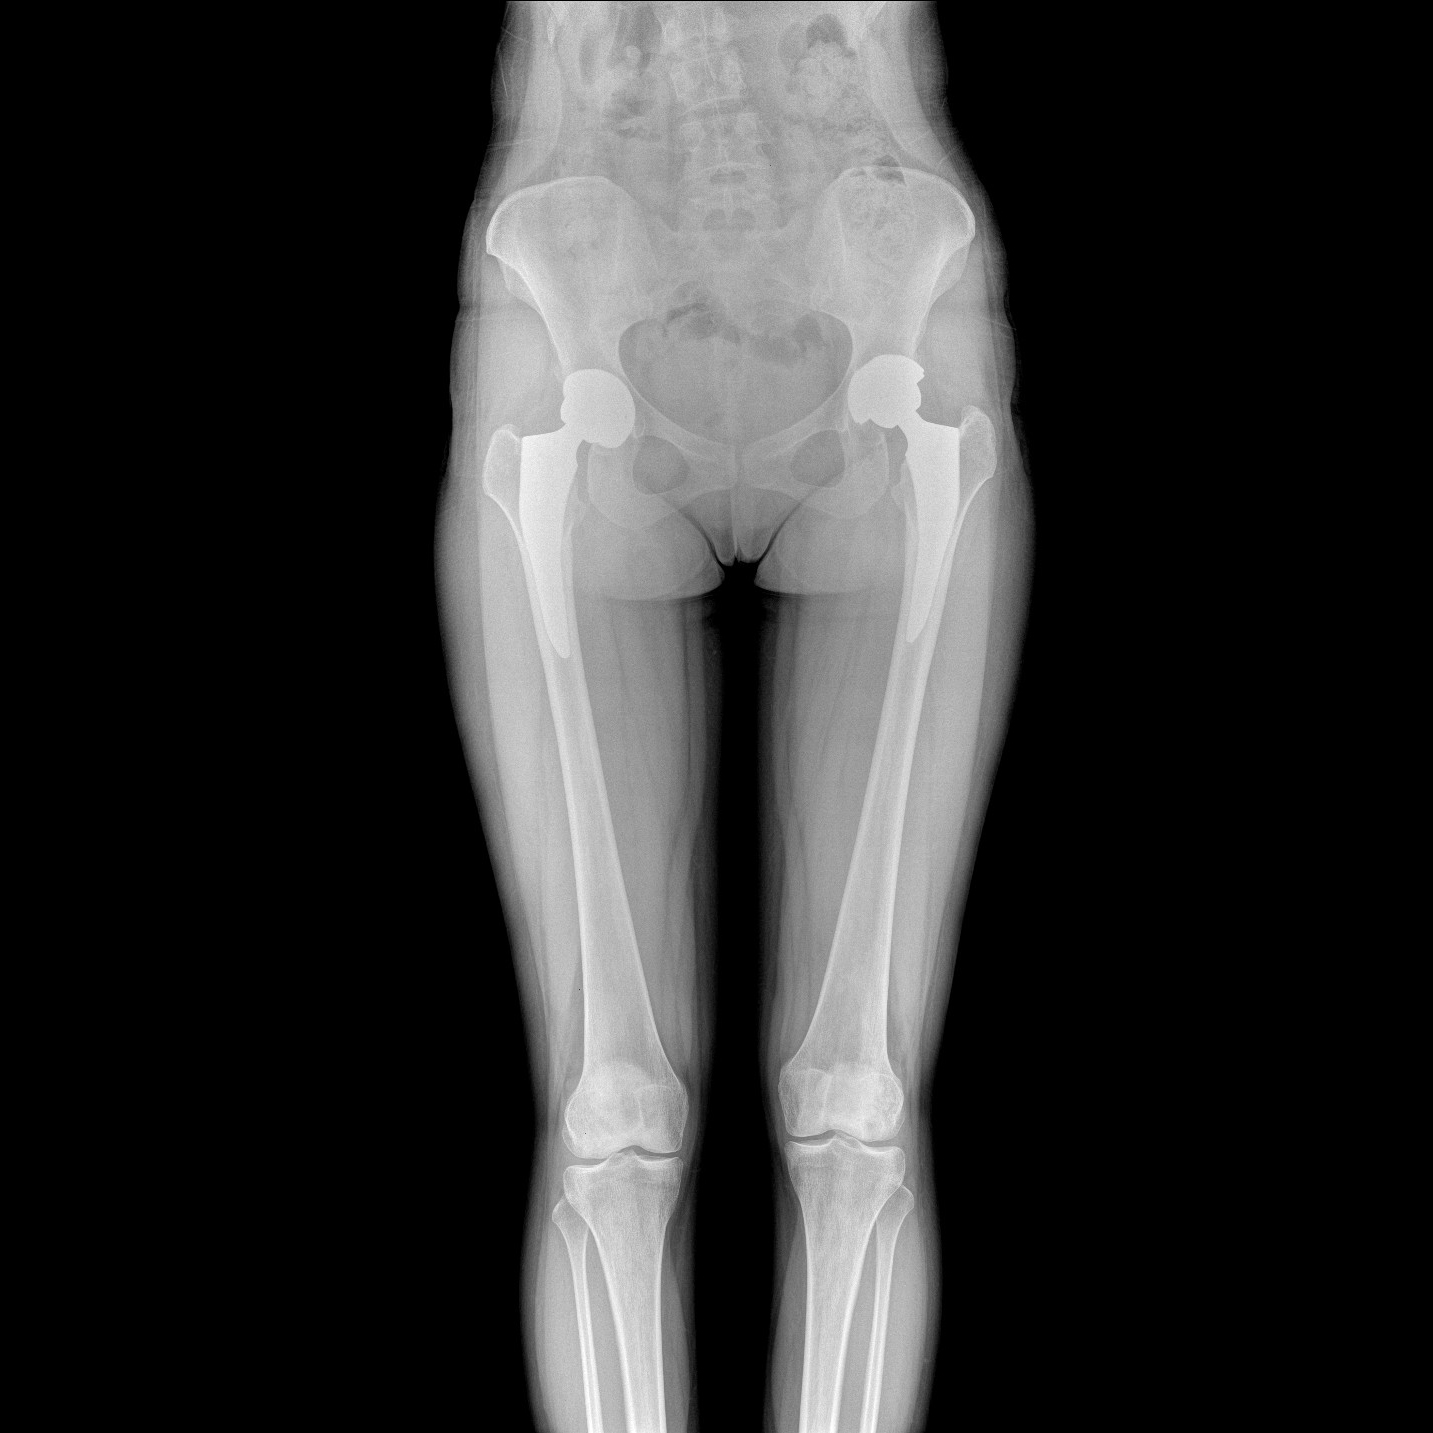

支持全脊柱攝影、雙下肢攝影、脊髓造影、復(fù)雜創(chuàng)傷、人工關(guān)節(jié)置換、關(guān)節(jié)損傷的修復(fù)重建等大視野臨床應(yīng)用

17"*34"有效視野,一次成像不拼接。相較于多張攝影再軟件拼接的DR設(shè)備,PLX8600解決了拼接圖像存在密度不均勻,拼接處圖像配準(zhǔn)和放大效應(yīng)等問題,給臨床帶來了大視野影像解決方案,可一次性覆蓋全脊柱或雙下肢影像。